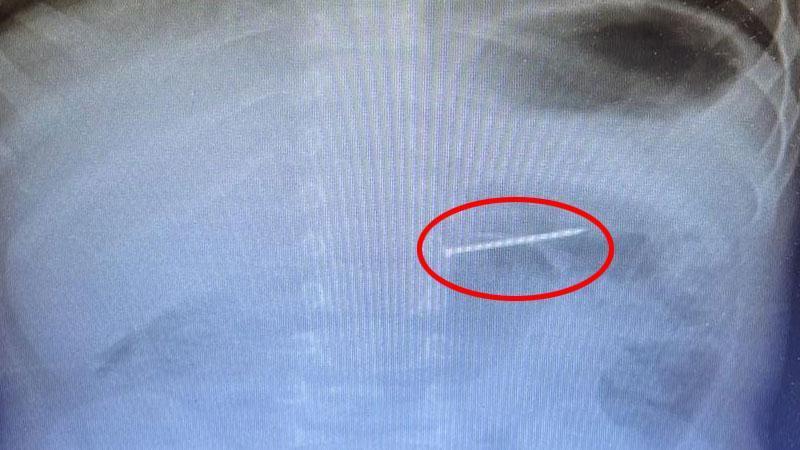

Burdur'un Bucak ilçesinde 2 yaşındaki çocuğun yuttuğu 4 santimetre uzunluğundaki çivi, Isparta'da gerçekleştirilen endoskopik işlemle çıkarıldı.

Burdur'da 2 yaşındaki bebeğin çivi yuttuğunu fark eden aile, durumu 112 Acil Çağrı Merkezi’ne bildirdi. İhbarla ailenin bulunduğu adrese sevk edilen sağlık ekipleri, bebeği ambulansla hastaneye kaldırdı. Isparta'daki Süleyman Demirel Üniversitesi Hastanesi'ne sevk edilen bebek, endoskopi ve çocuk gastroenteroloji birimi tarafından değerlendirildi. Sağlık görevlilerinin yaptığı radyolojik görüntüleme ile cismin midedeki yerleşimi saptandı ve endoskopik işlemle yaklaşık 4 santimetre uzunluğundaki çivi çıkarıldı. İşlem sonrası herhangi bir komplikasyon gelişmeyen hasta, izlem amacıyla servise yatırıldı ve kısa süreli takip sonrasında da taburcu edildi.